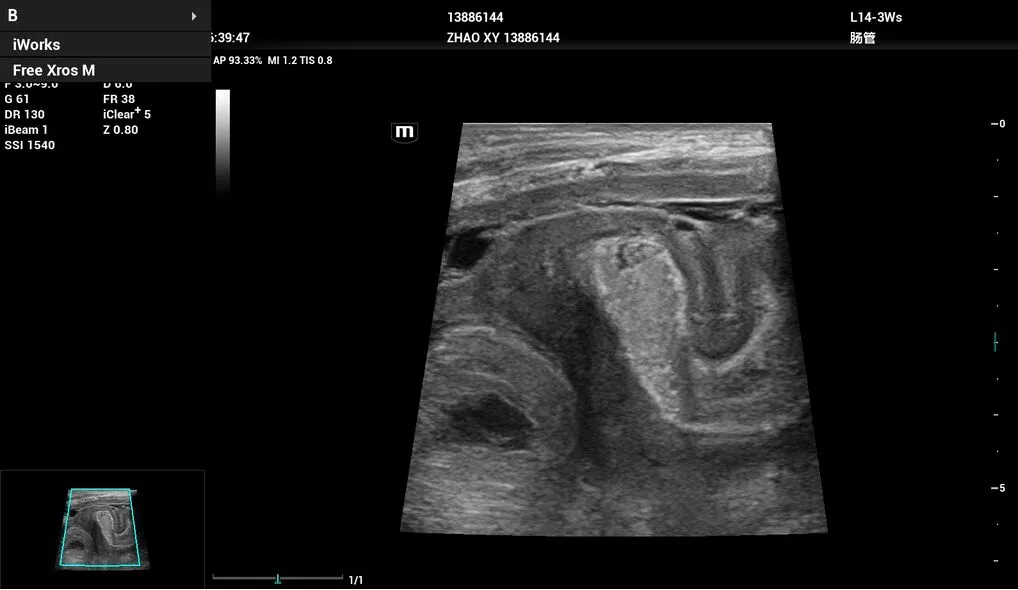

- L14-3Ws – линейный датчик для исследования сосудов, органов брюшной и грудной полости, педиатрии.

Кишечный тракт, 2D, L14-3Ws